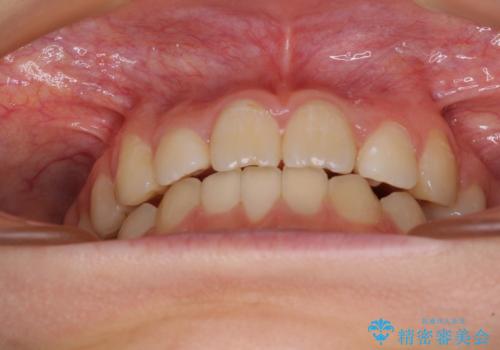

まずは補助装置を用いて八重歯を改善し、インビザラインにて歯列を整えましたが、当初の懸念が的中し、臼歯部の咬合を安定させることができませんでした。

海外留学の予定もあったため、後半は上下ワイヤー装置にて矯正治療を継続し、違和感なく咬合させることとなりました。